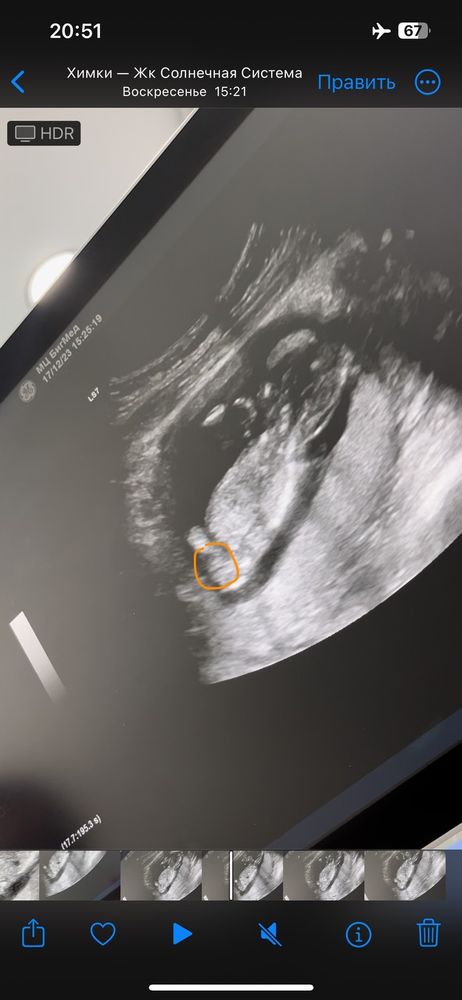

Пол малыша

Исполнилось желание)). Доктор сказала 98% что девочка 😁 как думаете можно уже гендер пати на нг устроить? 😁

На таком сроке конечно сомнительно, но правда похоже на девочку, я вчера была на 3 скрининге и тоже показывали такую "розочку"))) только чётче гораздо

Даша, она потом мне тоже четко ее показала) ну вот прям не перепутать) это просто фрагмент заскринила из видеозаписи ))) спасибо вам))

Мама_Амалии, ну да, там кофейне зернышко вроде как проглядывается)))